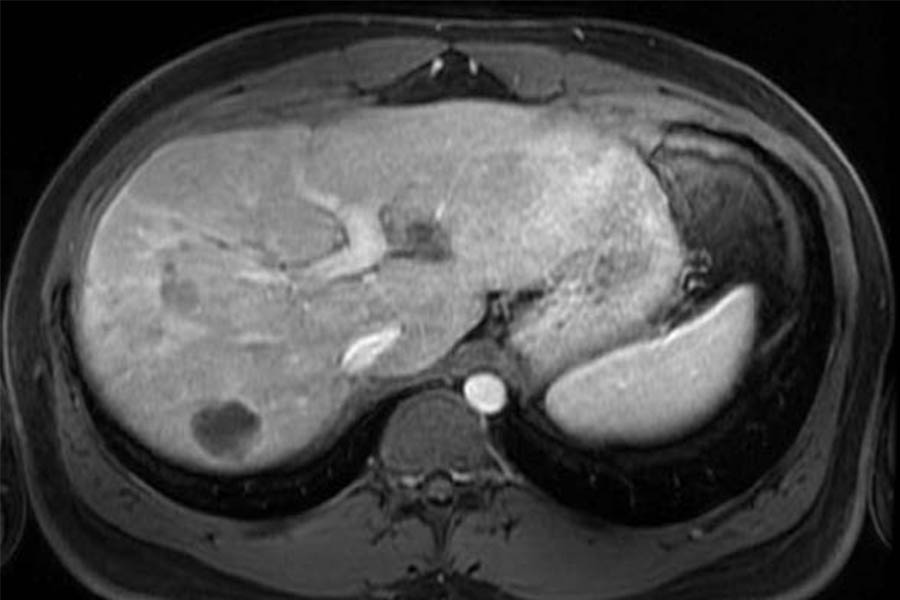

A Promising Approach for Colorectal Cancer Liver Metastases

NewYork-Presbyterian/Weill Cornell Medicine offers patients with colorectal cancer liver metastases access to a multidisciplinary treatment approach to address their disease. Transplant surgeon Dr. Juan Rocca leads the use of liver transplants to treat colon cancer when it has metastasized to the liver. By terminating the disease in the liver, patients do not have to depend on systemic treatments to control the progression. Dr. Rocca pairs this approach with the use of liquid biopsies, led by oncologist Dr. Pashtoon Kasi, which allows doctors to determine the genetic makeup of cancers quickly, track progress over time, and monitor for recurrence. This unique approach helps significantly prolong patient survival and improve quality of life.